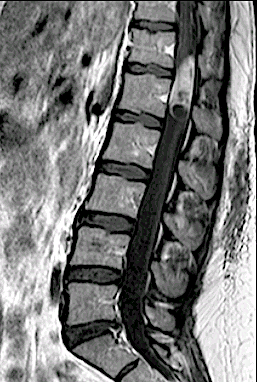

Paciente 73 años con lumbalgia inespecífica asociada a disestesias ocasionales en L3 derecha.

En este caso, a diferencia del caso «Schwannoma lumbar (L3, “raíz no elocuente” ), se optó por un abordaje longitudinal medial con laminotomía + laminoplastia L1 y resección parcial lámina Th12.

Control RM postoperatorio con exéresis completa. Obsérvese el trazo de la laminotomía con la integridad de grupos musculares.